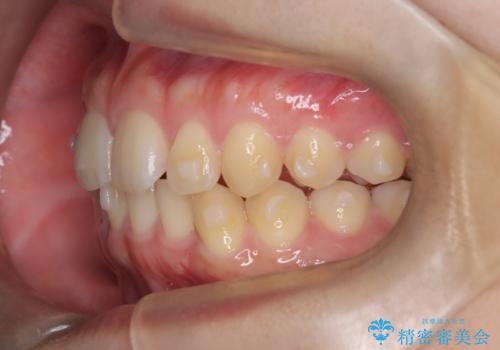

マウスピース矯正で前歯のガタツキを改善! 短期間で治療完了

- 前歯のガタツキが気になるとのことで来院されました。

マウスピース矯正で治療することとしました。